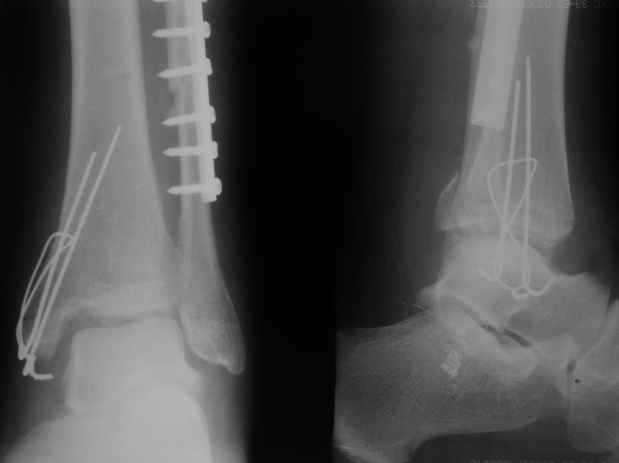

Перелом типа Вебер С с эверсионным механизмом травмы всегда сопровождается повреждением дистального межберцового синдезмоза, поэтому вместе с фиксацией переломов лодыжек( малоберцовой кости) автоматом выполняется фиксация синдесмоза винтом, который обычно удаляется через 8 недель -

перед началом полной нагрузки на ногу.

С мнением «провести позиционный межберцовый винт чуть ниже пластинки в положениий тыльного сгибания стопы» согласен, но я бы нагрузку начал через три недели и удаление шурупа можно провести через 6-8 недель.

Для облегчения удаления сломанных шурупов (случается часто) рекомендую фиксацию двумя 3.5мм кортикальными шурупами на 3 мм длиннее, тот же сломанный шуруп легко удаляется с медиальной стороны.

Здесь похожий случай трехнедельной давности, перелом почти сросся и была укорочена малоберцовая, на операции длину малоберцовой смогли восстановить только после того, когда проксимальнее пластины ввели шуруп и использовали его как толкатель, с помощбю дистракционого инструмента (lamina spreader).

Меньше всего волнует положение медиальной лодыжки - в любое время можно провести остео или реостеосинтез, при несращении можно просто резецировать без ущерба для движений в голеностопе. Здесь обошлись фиксацией одним 4 мм канюлированным шурупом.